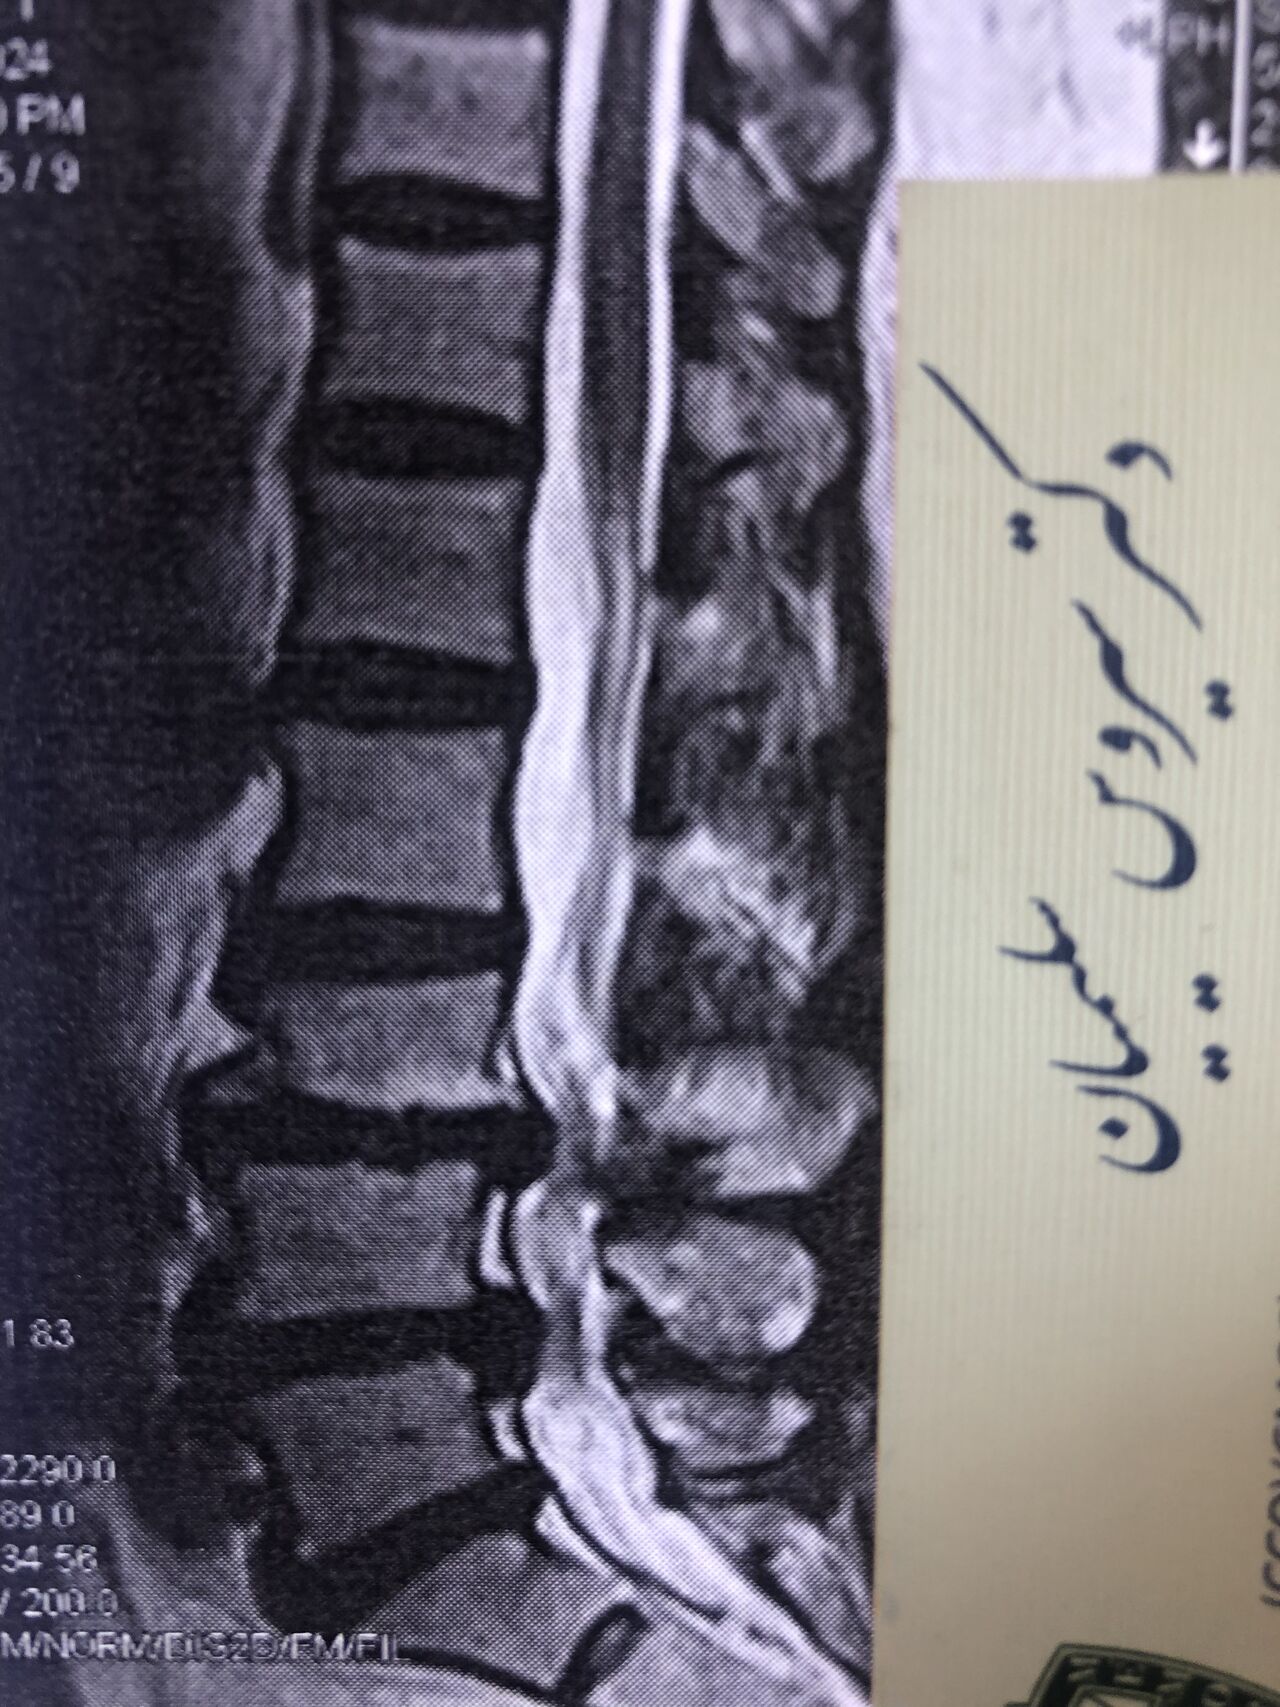

Case 7

60 years old female patient presented to my clinic today,

May 31/2025 with R. Chronic pelvic pain which gets aggravated by walking. Her lower extremity motors all were fine

She has had chronic neck pain as well with radiation to R Upper extremity

I would like to show especially to new grads some information and improve their x ray and mri readings

Would be so great to hear from chiropractic doctors or any other specialist other findings we may have missed

Findings:

L4-L5 level:

sever L4-5 canal stenosis mainly due to FL hypertrophy?

CSF block. Mild L3 retrolisthesis, facets hypertrophy bilateraly causing L and R IVF stenosis, disc hyperbule

Since I’ve noticed instability in some segments I asked for dynamic L/S x ray:we see mild L4 ant listens due to DjD/DDD. There is not any pars defect.

In cervical mri I marked some findings plus their reports

I will give her treatment via Cox chiropractic flex dis and axial decompression. I would use DTS decompression

Since there is a few mild to moderate DjDs/ DDs in her lower back I won’t use lumbar adjustment on her